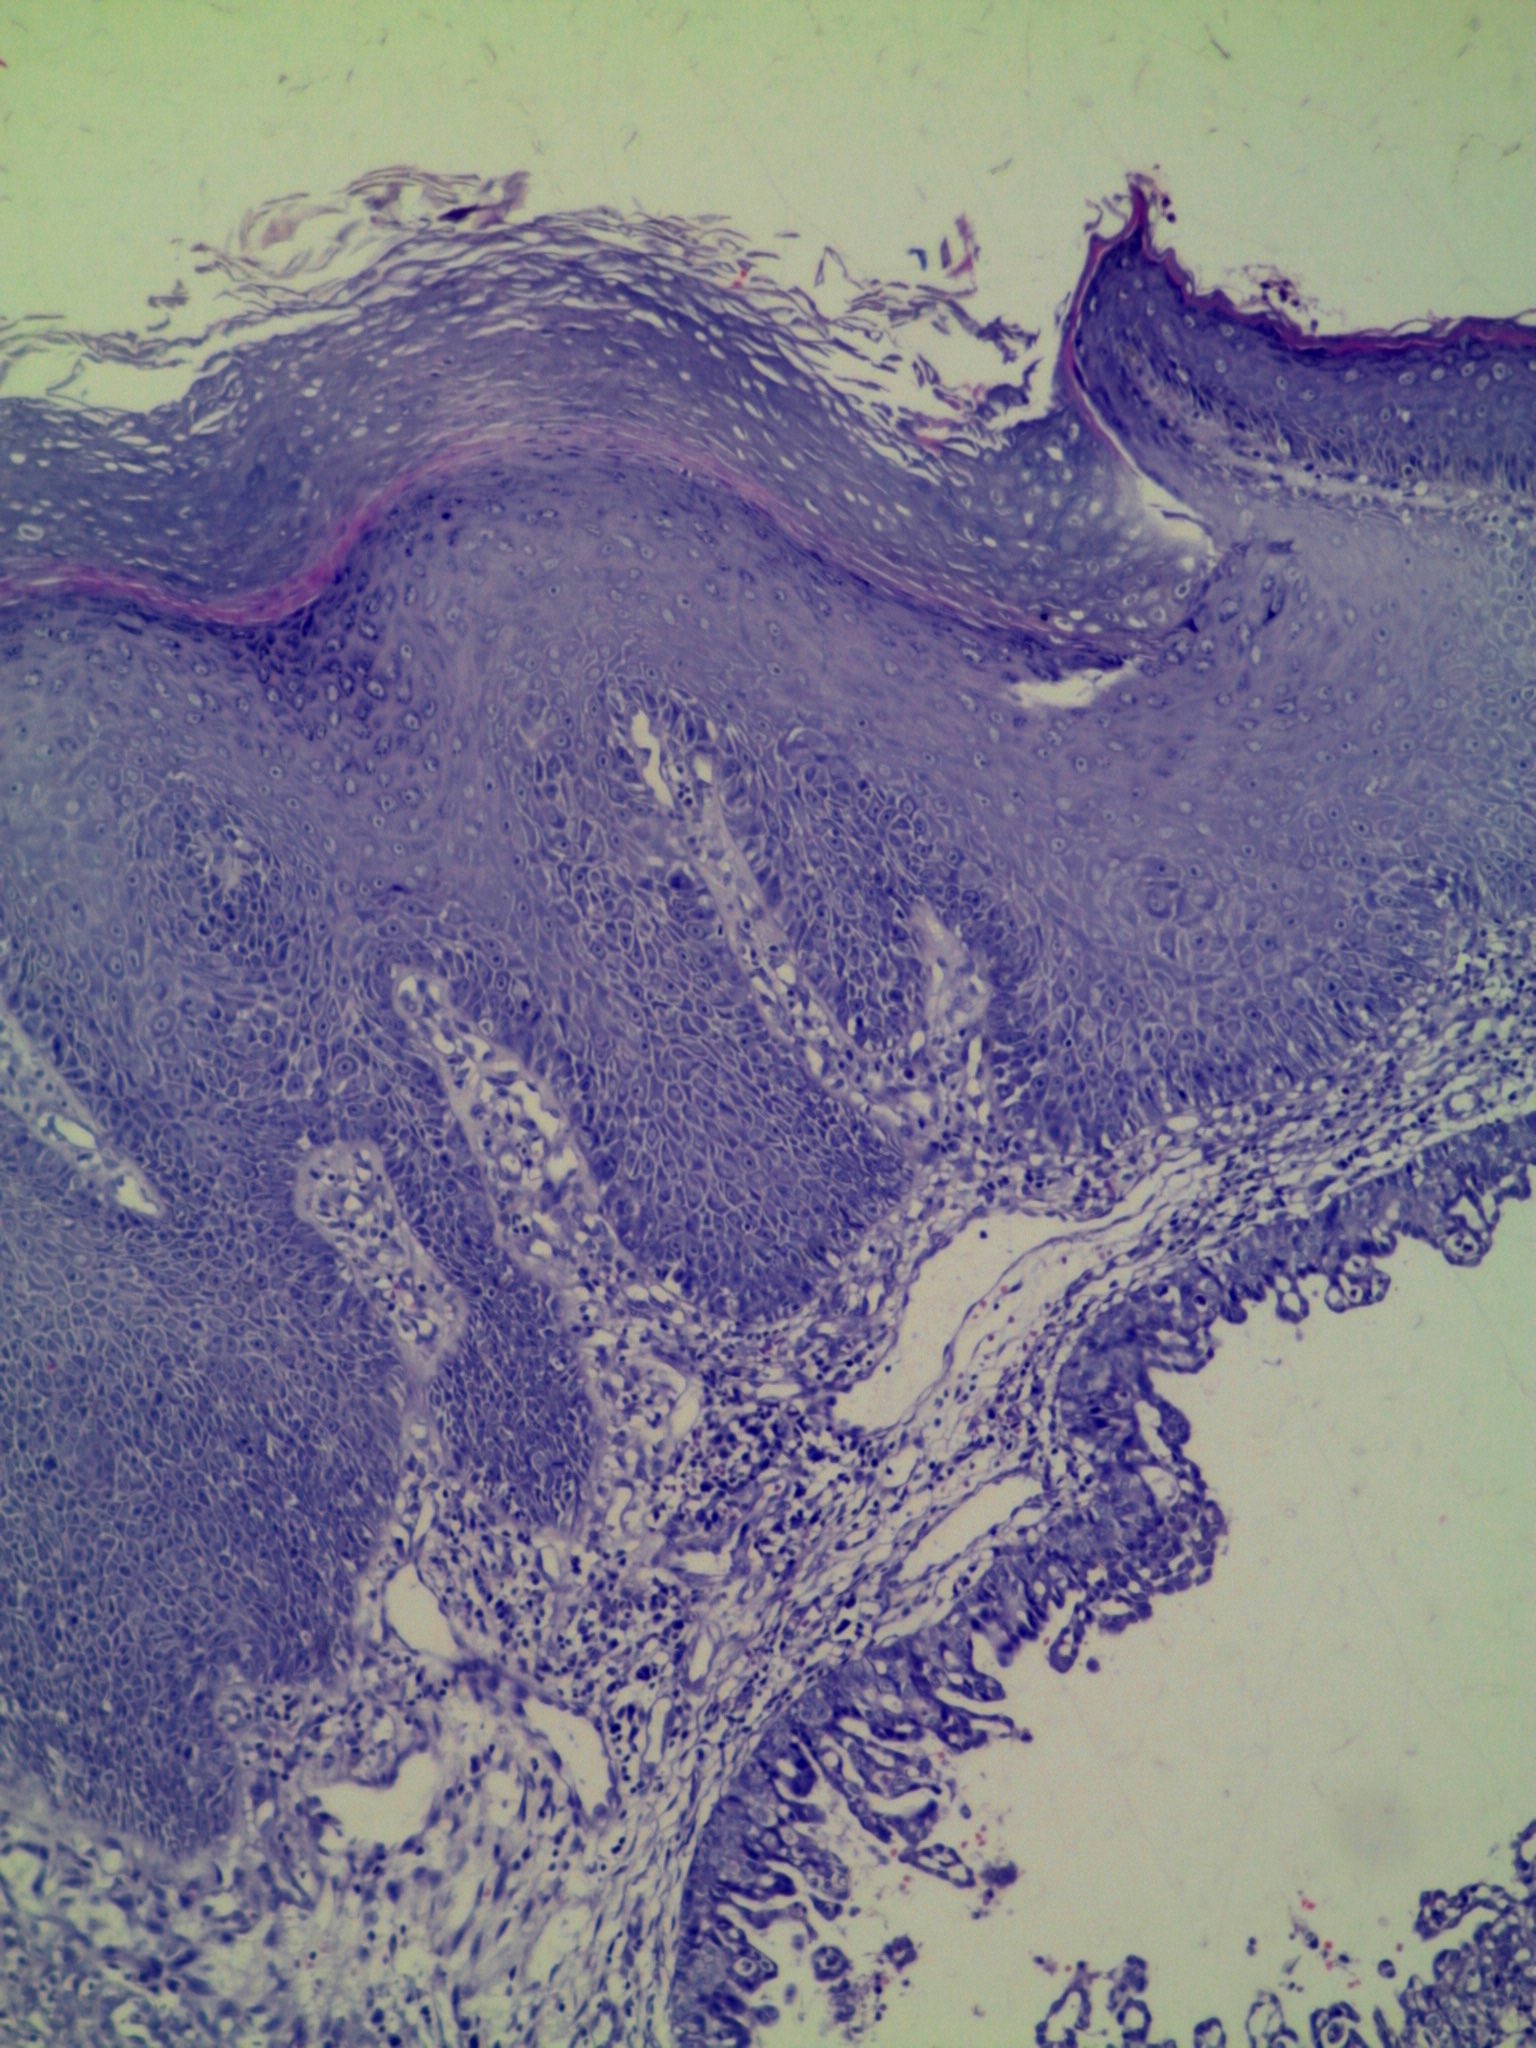

Papillary syringocystoadenoma is an uncommon benign adnexal neoplasm, which is preferentially located on the scalp and face, and is associated with sebaceous nevus in 40% of cases. Although rare, its transition to basal cell carcinoma and ductal carcinoma may occur. The authors describe the case of a 7-year-old male patient with a linear papular dermatosis in the neck from birth. Dermatological examination showed erythematous, crateriform, confluent papules, arranged in a band, 3 x 2 cm in the cervical region. The lesion was excised for therapeutic and diagnostic purposes. Histopathology demonstrated epidermal cystic invagination and papillary projections surface by glandular epithelium, with decapitation secretion and abundant lymphoplasmocytic infiltrate. The clinical and histological findings were compatible with the diagnosis of papillary syringocystoadenoma. Despite the clinical variability of this entity, the histopathology is characteristic and the treatment consists in the excision of the lesion.